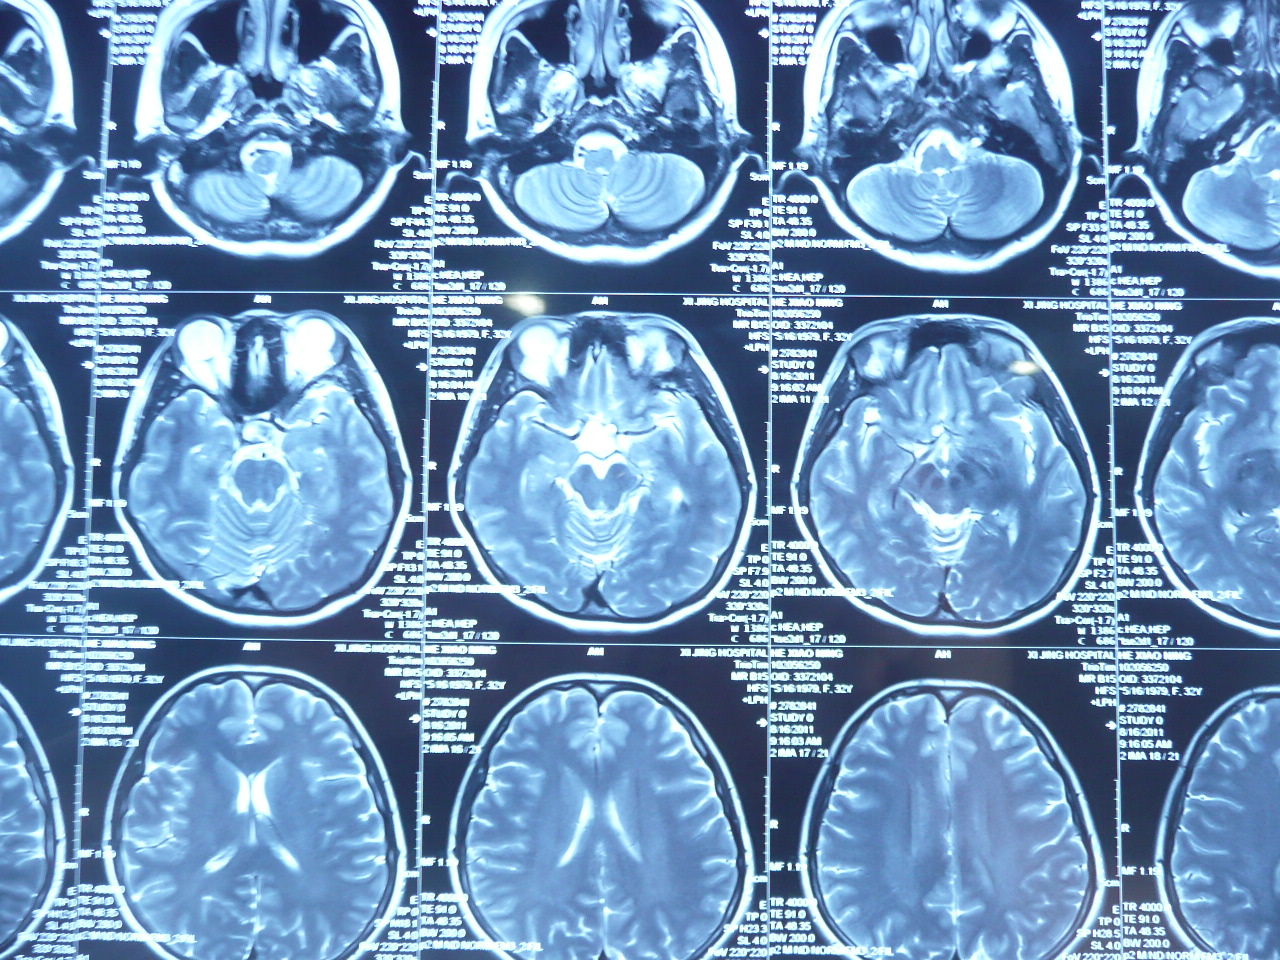

6种鞍区常见囊性病变的ct鉴别

图片尺寸271x306